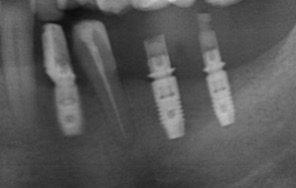

多顆植牙補骨重建-陳珮儀醫師

因嚴重牙周病造成大範圍的骨頭喪失,透過補骨再生方式重建,

最後以人工植牙重建齒列

治療前

治療後